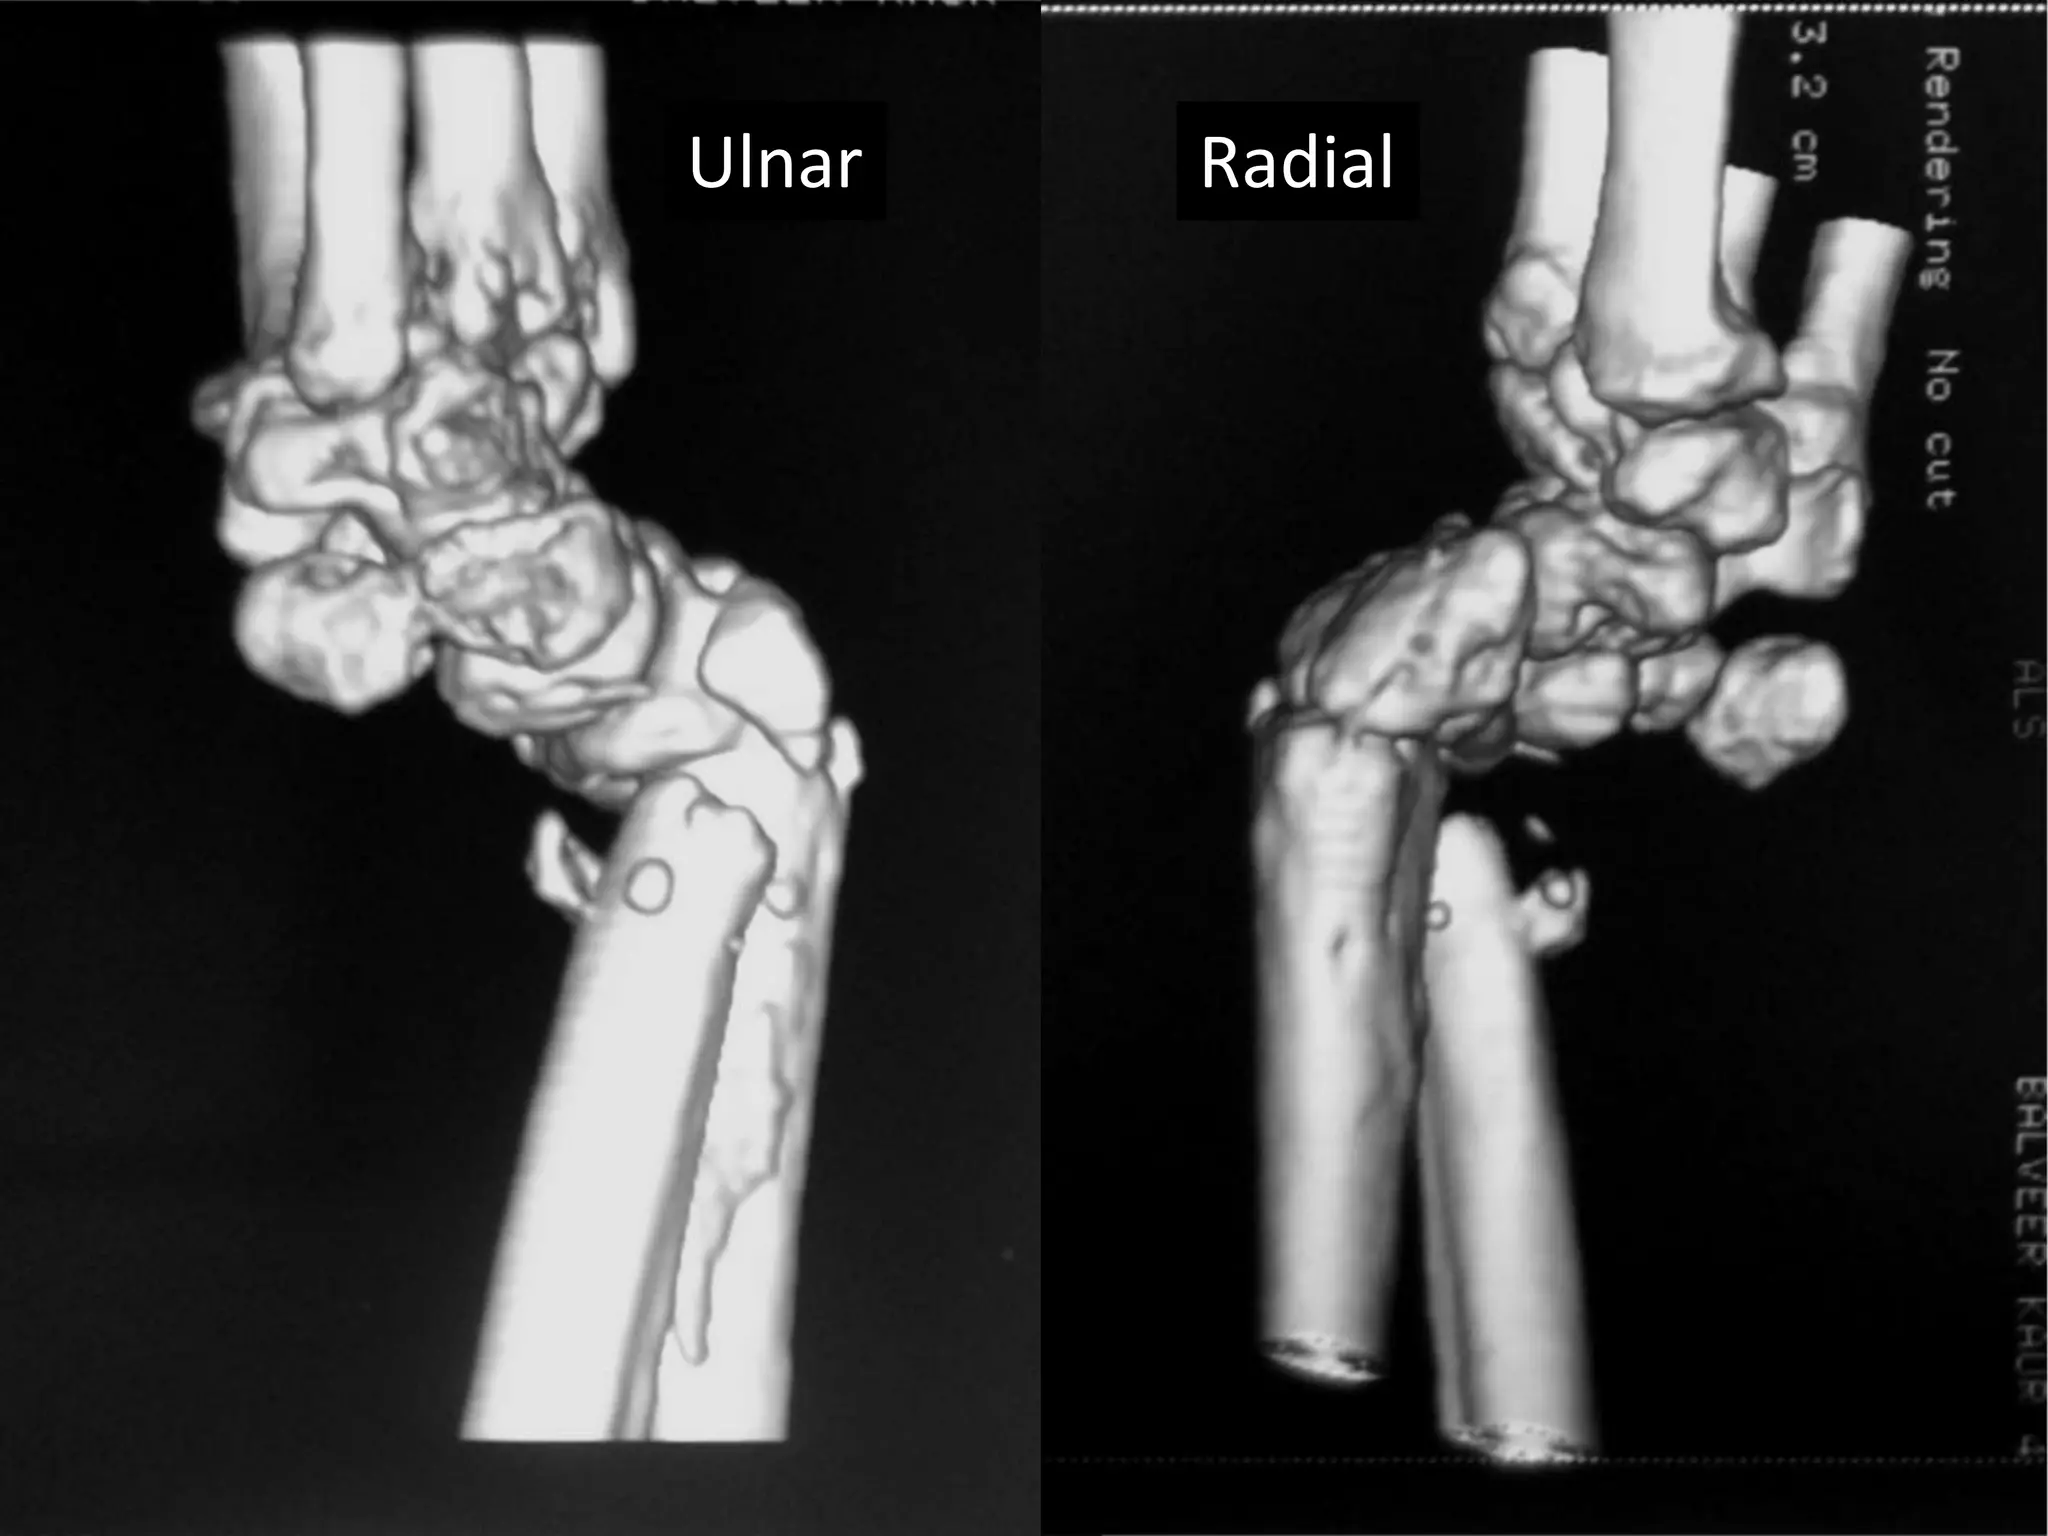

Severe Palmer flexion and ulnar deviation deformity

Dorsal

Palmer/voral

Ulnar Radial

Palmer surface

Severe Palmer flexionand ulnar deviation deformity